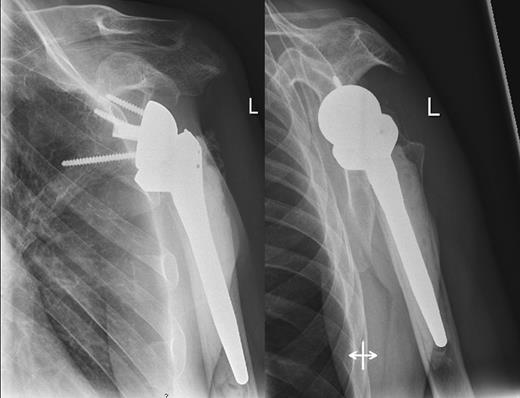

A 48-year-old patient was referred to a level I trauma center after the first incidence of an epileptic convulsion. The patient was alert and oriented with retrograde amnesia from the time of convulsion. Peripheral neurology was normal. The X-rays showed bilateral posterior shoulder dislocation with fractures of both humeral heads (Fig. 1). A CT of the head and both shoulders was performed to exclude intracerebral pathology and to achieve better demonstration of the shoulder fractures (Fig. 2). According to the AO fracture classification, he had a 11-C3.1 fracture on the left side and a 11-C3.3 fracture on the right side. The right side fracture was treated with a cementless hemiarthroplasty (OrTra®, Zimmer, Germany), while an open reduction and internal fixation (ORIF) with an angular stable plate (Philos®, Synthes, Germany) was performed on the left. Despite the high incidence for humeral head necrosis after ORIF in this fracture type, this option was chosen based on the young age of the patient. Postoperative X-rays and CT showed adequate positions of the implants (Fig. 3). The shoulders were immobilized in Gilchrist bandages followed by passive mobilization for the first 6 weeks by physiotherapy with a limitation for abduction and anteversion to 90°. There were no complications intraoperatively or in the first postoperative time. Patient was discharged after 8 days. Antiepileptic therapy was initiated with 5 mg clobazam and subsequent increasing doses over the following weeks. There were no more signs of epilepsy in the follow-up. A CT 4 months after operation showed dislocation of a fragment on the left side which was subsequently resected. At the 1-year postoperative review, the patient showed impingement of the left shoulder with abduction limited to 50° by both the plate and an osteophyte. Radiological assessment revealed signs of necrosis of the head. The plate was removed and the osteophyte resected. Eighteen months after injury, the left shoulder showed progressive avascular osetonecrosis of the head (Fig. 4) and after plate removal an inversed prosthetic replacement had to be performed (Fig. 5). At the last follow-up 3 years after injury, the patient was free of pain with a bilateral range of motion of 90° abduction and elevation.

Postoperative X-rays after hemiprothetic replacement on the right and angle stable plate osteosynthesis on the left side.